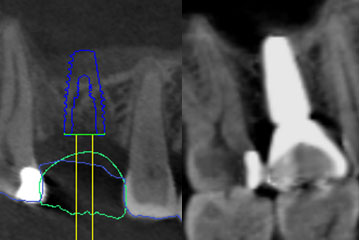

There is a misconception that wisdom teeth always need to be removed. The reality is that, this is not always the case, even if the wisdom teeth are causing swelling and pain.

Sinus Lifting for Dental Implants